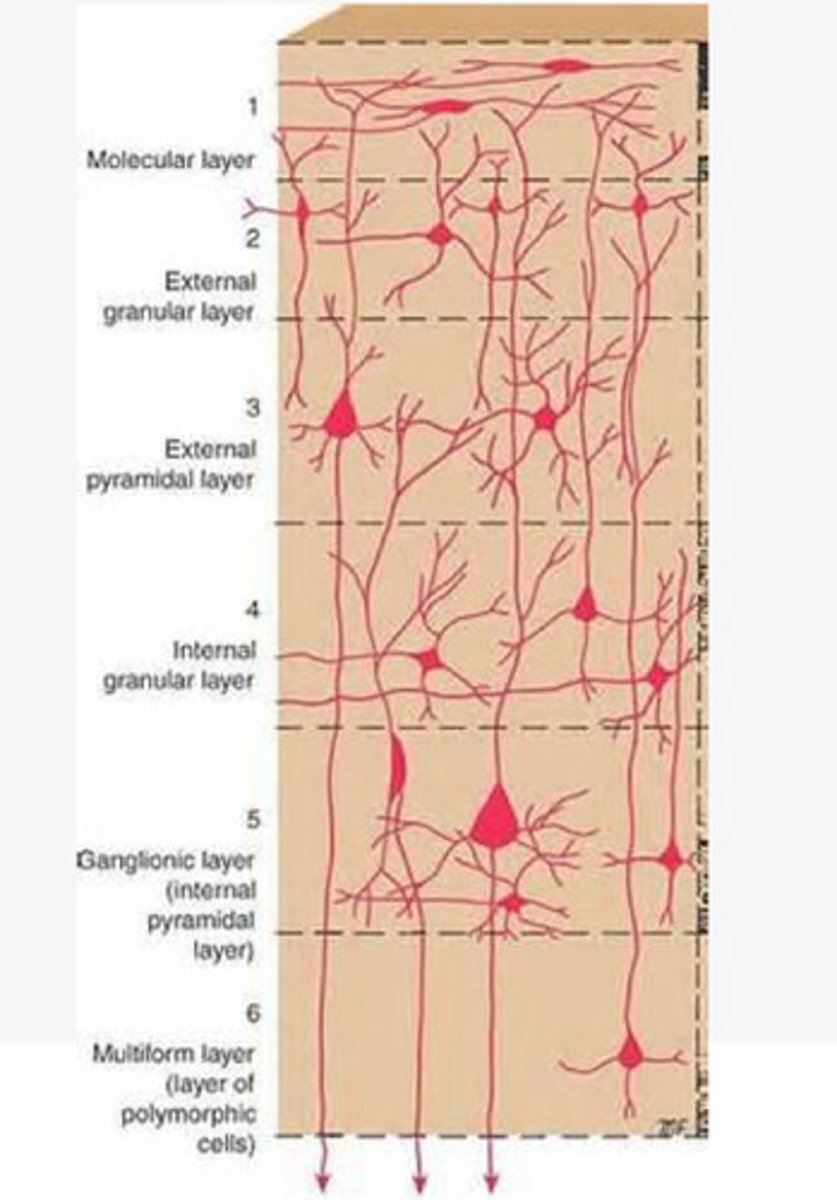

divided into 6 distinct layers, due to varying densities of cell body types within each layer

The cortex of the brain is divided into how many layers? Why is it divided into layers?

Layers of the cortex of the brain pic

2 and 4

What are the layers of the cortex that are associated with input?

3 and 5

What are the layers of the cortex that are associated with output?

molecular layer

What is the name of Layer 1 of the cortex of the brain?

very few cells

Does Layer 1 of the cortex have a lot or few cells?

receives dendrites from internal layers so it may actually function as a coordinating center where layers can communicate action

What does Layer 1 of the cortex do?

1

Every layer sends densities to Layer ____?

1

What layer serves as the "water cooler" of the brain?

external granular layer

What is the name for layer 2 of the cortex of the brain?

receives input from other cortical regions

What is the function of Layer 2 of the Cortex of the brain?

Stellate

What type of cells (stellate/pyramidal) would be most concentrated in Layer 2?

external pyramidal layer

What is the name for layer 3 of the cortex of the brain?

sends output to the other cortical layers

What is the function of Layer 3 of the cortex of the brain?

pyramidal

What type of cells (stellate/pyramidal) would be most concentrated in Layer 3 of the brain?

Layers 2 and 3

What layers are associated with association and commissural fibers?

Layer 3 - axons of cell bodies

Layer 2 - synapse into target areas in Layer 2

What part of the axons is in Layer 2/ in layer 3?

Layer 3 - external pyramidal layer

All axonal cel bodies for association and commissural fibers lie within what layer of the Cortex of the brain?

internal granular

** or called the striate cortex because it is so thick that you can see a line through this layer even in unstrained brain slides

What is the name for the 4th layer of the cortex of the brain?

receives input from the thalamus, geniculocortical layer, and other brainstem areas

What is the function for the 4th layer of the Cortex of the brain?

very thick within the vision, auditory, and somatosensory areas

Is Layer 4 thick or thin within SENSORY areas of the cortex?

Internal pyramidal

What is the name for Layer 5 of the cortex of the brain?

sends axons to the brainstem (corticobulbar) and spinal cord (corticospinal)

What is the function of Layer 5 of the cortex of the brain?

in motor areas of the cortex?

Where is layer 5 very thick in the brain?

the frontal lobe -- very motor heavy

What lobe of the brain will have a thick layer 5 of the cortex of the brain?

the multiform layer

What is the name of layer 6 of the cortex of the brain?

-sends axons back to the thalamus through corticogeniculate fibers

-modulates what information the thalamus sends to the cortex to control the strength of the signal received and modulate what you pay attention to

What is the function of layer 6 of the cortex of the brain?

no

Is layer 6 a motor layer?